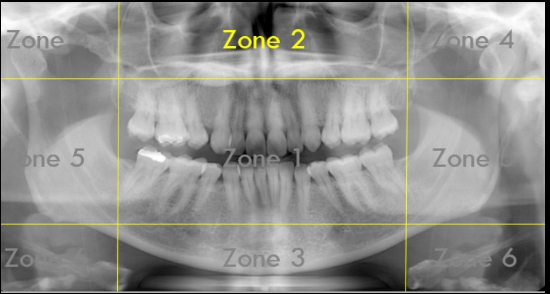

Identify The Zones.

Zone 1: Dentition

Zone 2: Nasal Cavity and Maxillary Sinuses

Zone 3: The Mandible

Zone 4: Temporomandibular Joints (TMJs)

Zone 5: Spine and Ramus

Zone 6: Hyoid Bone

What Zone Is This?